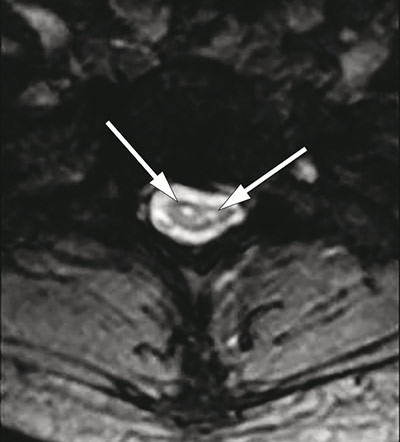

MR av ryggmargen viste markert atrofi fra nivå C4 til Th2 og to langsgående symmetriske T2-vektede høysignallesjoner fra nivå C2 til Th2 (fig 3, fig 4), lokalisert til området for anteriore horn i medulla. Forandringene ble ikke oppfattet å være forenlig med syringomyeli, demyeliniserende plakk, tumor eller transvers myelitt. Det var normale funn ved MR caput.

Petiot og medarbeidere (12) publiserte i 2000 en kasuistikk av en 41 år gammel kvinne med O’Sullivan-McLeod-syndromet. Pasienten hadde over en periode på 20 år utviklet en langsomt progredierende asymmetrisk svakhet i begge hender. Det var ingen nevrologiske sykdommer i slekten. MR av cervikalcolumna avdekket symmetriske høysignallesjoner på T2-vektede bilder, svarende til et område av forhorncellene som strakte seg fra nivå C6 til C7. Diameteren av cervikalmedulla ble vurdert som normal.

O’Sullivan-McLeod-syndromet er en sjelden form for distal spinal muskelatrofi med forholdsvis god prognose. Diagnosen bygger på kliniske og nevrofysiologiske undersøkelser og karakteristiske MR-forandringer med segmental atrofi i cervikalmedulla og høysignallesjoner i området svarende til fremre motornevron.